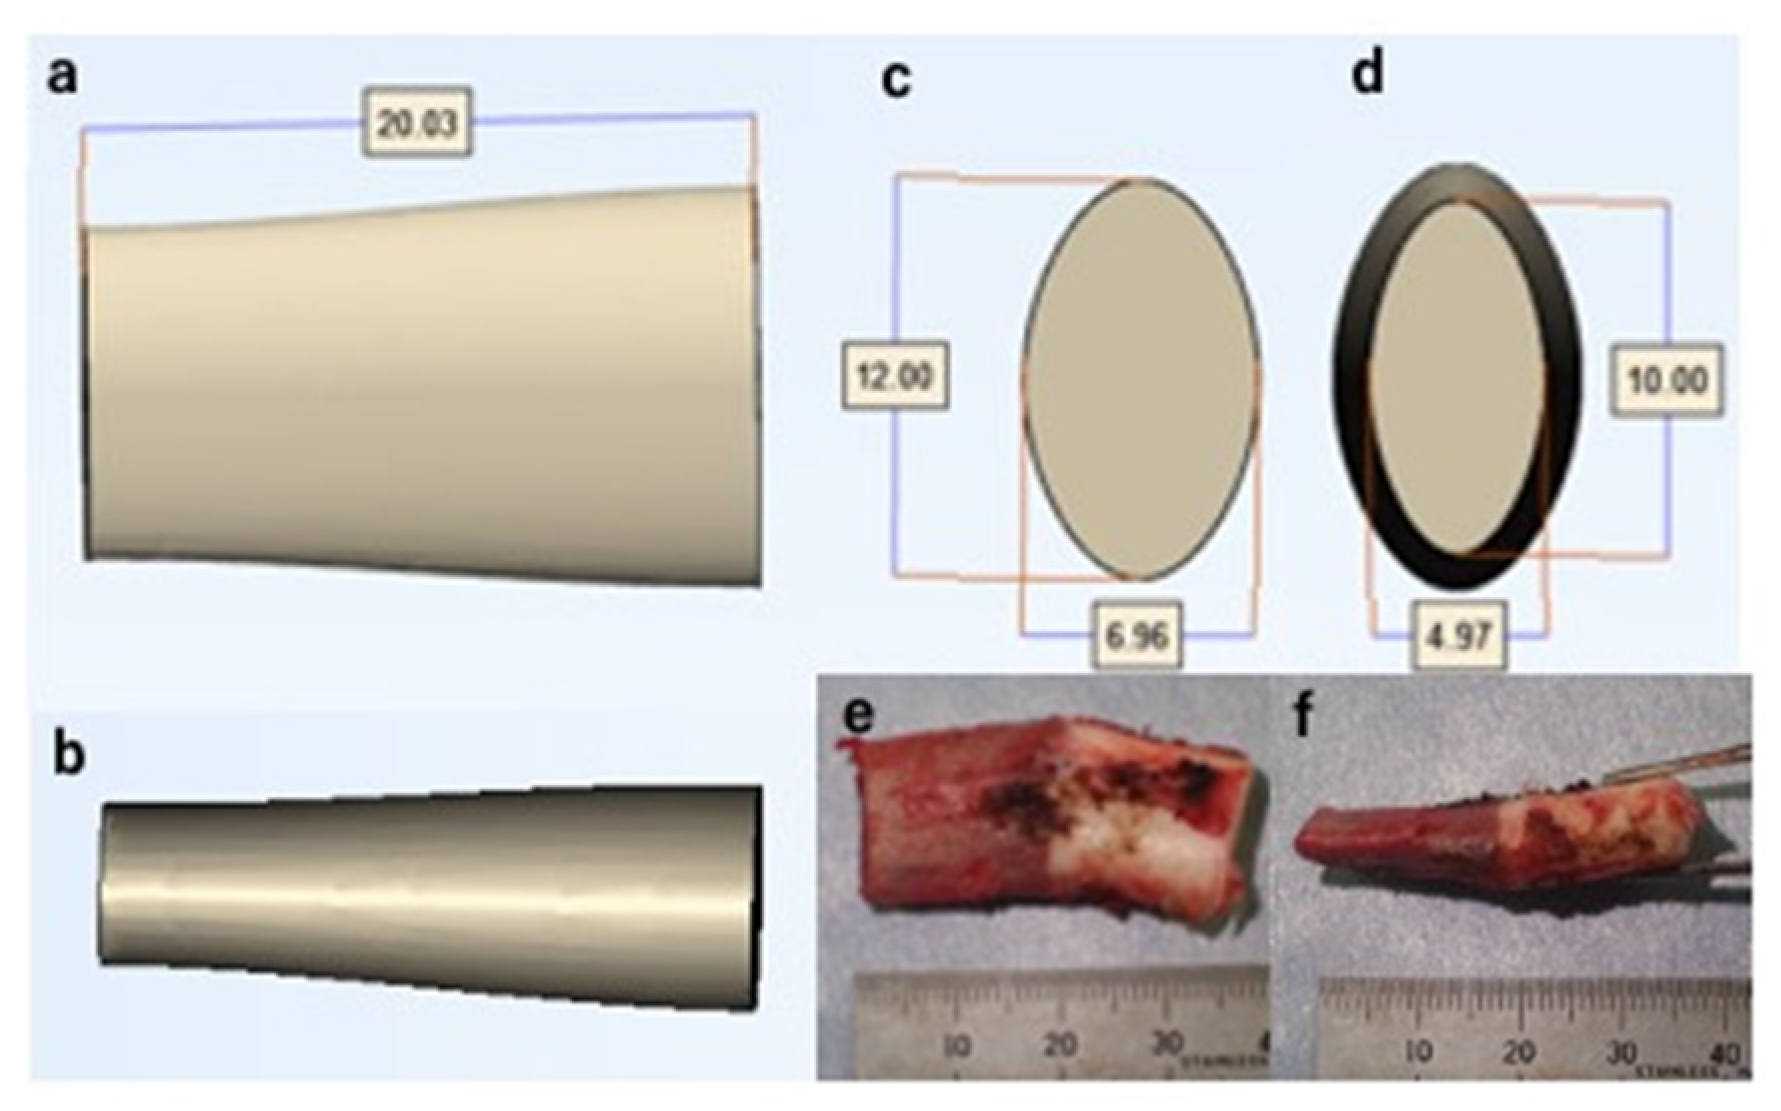

2.6. Surgical Simulation

3.3. Surgical Simulation